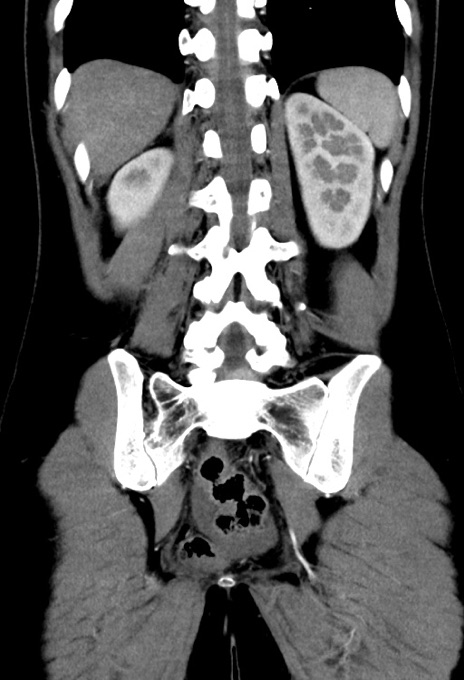

横断像

【症例】20歳代女性

【主訴】嘔吐、下腹部痛

【現病歴】昨日夕食後に嘔吐し下腹部痛が出現。本日になっても嘔吐持続し改善しないため来院。

【身体所見】意識清明、BT 37.2℃、BP 108/67mmHg、腹部:平坦、やや硬、下腹部正中から右にかけて圧痛あり、反跳痛軽度あり、tapping pain(+)。

【データ】WBC 13600、CRP 14.94